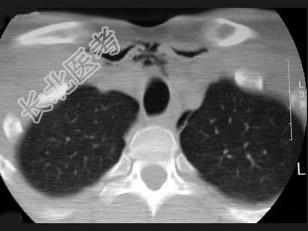

- 多项选择题男,27岁, 开车外出在高速行驶时翻车,呼吸困难, 喉部肿胀,CT检查如图所示, 正确的描述或诊断是 ( )

A、左侧甲状软骨骨折

B、左侧梨状窝软组织肿胀

C、颈部、胸骨下方软组织积气

D、左侧杓状软骨骨折

E、考虑喉、气管破裂